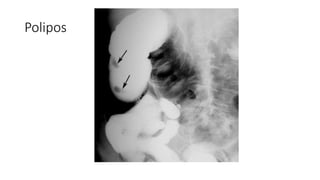

• Polipos

• Adenomatoso: origen epitelio glandular

• Hiperplasicos: pequeños (5mm)

• Harmatosos: en niños y adultos jóvenes en recto o sigmoides. Pedunculados

• Colon por enema: doble contraste para estudiar mucosa. Valora si son sésiles

o pedunculados, mucosos o submucosos

• Colonoscopia por TC: detecta pólipos mayores de 6mm

Polipos

• Polipos • Adenomatoso:origen epitelio glandular • Hiperplasicos: pequeños (5mm) • Harmatosos: en niños y adultos jóvenes en recto o sigmoides. Pedunculados • Colon por enema: doble contraste para estudiar mucosa. Valora si son sésiles o pedunculados, mucosos o submucosos • Colonoscopia por TC: detecta pólipos mayores de 6mm